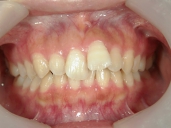

矯正歯科 治療前 正面